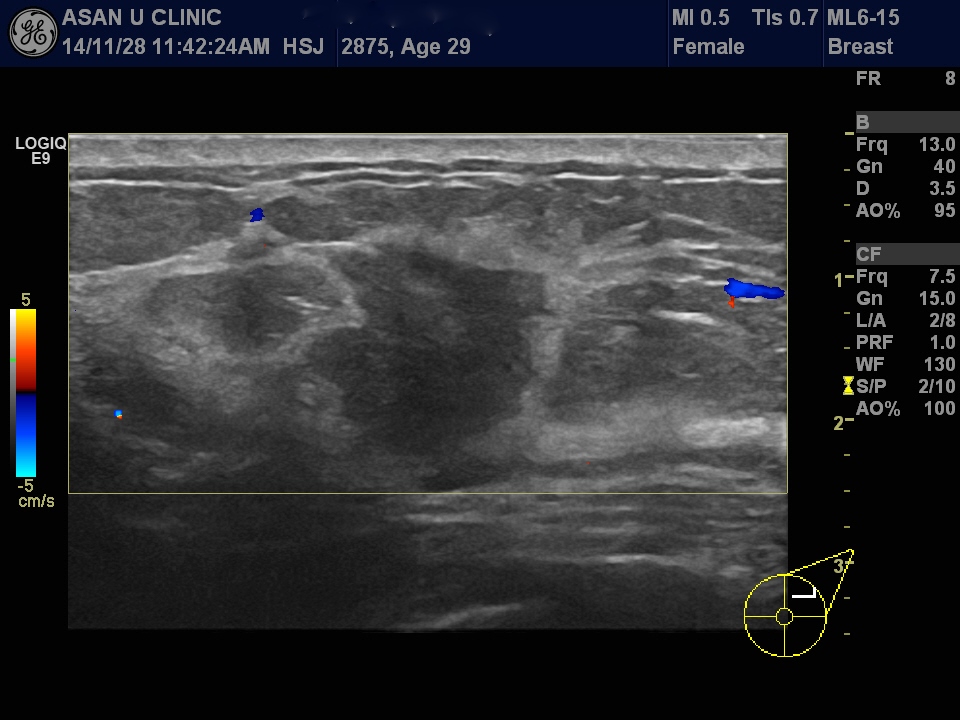

한달전부터 좌측유방에 통증과 함께 멍우리가 잡혀 내원한 만29세 여성입니다.

조직검사상 침윤성 유관암이었고 다행이 혹의 크기가 크지 않아 초기일것으로 예상됩니다.

드물지만 30대 미만의 유방암이 이렇듯 있습니다.